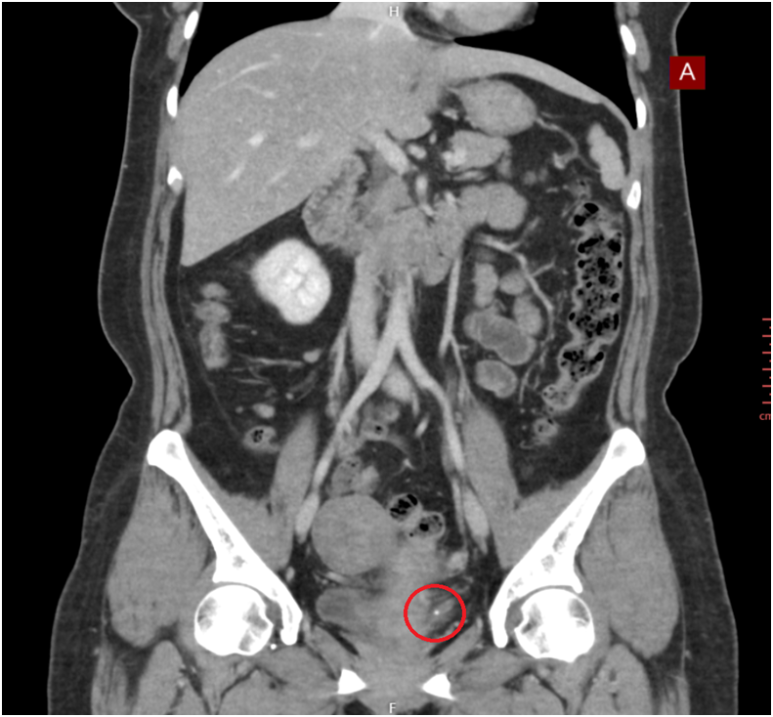

게실염, 충수염, 하복부통증 증상의 원인을 정확하고 신속하게 진단합니다.

게실염, 충수염, 하복부통증에 통해 관련 사례를 확인하실 수 있습니다.